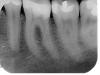

LenaSpb Опубликовано 24 сентября, 2007 Поделиться Опубликовано 24 сентября, 2007 В дек.2006 отвалился кусочек нижнего левого 6 зуба под пломбой в области контакта с 7кой, до этого там застревала пища. В февр.2007 в ниж.лев.6ке ощущалась боль при накусывании Соответствующий участок ортопантограммы (февр.2007) до лечения выложен по адресу: http://photofile.ru/users/lena-spb/3105329/65626972/ Через 3 месяца (апр.2007) мне его пломбировали. Удаляли ли мне тогда часть пульпы, было ли кровотечение, или даже до пульпы не дошли, я не знаю. При обработке полости была тень сомнения у стоматолога: "может быть, здесь придется нерв удалять… нет, пожалуй, можно оставить" Несмотря на анестезию ультракаином дс, при обработке полости я разве что не выла, чувствуя почти все манипуляции внутри той части зуба, которая ближе к контакту с 7. Стоматолог сказала, что такая чувствительность зуба говорит в пользу того, что лечение пройдет успешно и нерв удалять не придется. Итак, зуб запломбировали, сказали наблюдать. Ощущения сразу после пломбирования и до сих пор (не менялись): Чувствительность при надавливании на участок (четвертинку) жевательной поверхности зуба, который ближе к 7 и к языку. При накусывании совсем без пищи - боль и ощущение легкого хруста где-то в зубе. Зуб реагирует на холодное легким болезненным ощущением (даже не болью), которое проходит через 2-3 секунды после убирания холодного (если резко набрать в рот очень холодной воды, а через некоторое время выплюнуть ее, то ощущения в этом зубе заметно отличаются от ощущений во всех прочих зубах). Зуб реагирует на горячее легким болезненным пульсирующим ощущением, которое проходит через примерно 1 секунду после убирания горячего. Сам по себе зуб не болит ни в какое время суток, если его не трогать и не жевать им твердую пищу. Цвет зуба нормальный, не изменился Прицельный снимок, сделанный через 4 месяца после пломбирования выложен по адресу: http://photofile.ru/users/lena-spb/3105351/65625304 Хотелось бы снова обрести способность безболезненно жевать твердую пищу и на левой стороне. Но по возможности сохранить зуб живым. Глубокоуважаемые специалисты, можете ли Вы оценить по перечисленным симптомам, Каковы шансы того, что можно сохранить жизнеспособность пульпы? Можно ли до вскрытия полости зуба оценить состояние пульпы - живая? Некротизированная? Есть микробы? воспаление? Отек? Есть ли смысл сделать еще какую-то диагностику? Какую? Каковы этапы лечения, нацеленного на сохранение жизнеспособности пульпы? Сколько требуется посещений стоматолога и каковы промежутки между визитами? Через какое время можно было бы считать, что лечение прошло успешно? Спасибо. Ссылка на комментарий

Эльза Опубликовано 25 сентября, 2007 Поделиться Опубликовано 25 сентября, 2007 А можно и я спрошу? Пальцы-то чешутся еще со вчерашнего дня На этих сниках есть уменьшение размеров пульпарной камеры вот в этом самом проблемном зубе или нет? Ну ведь правда есть? Ссылка на комментарий

NataLee Опубликовано 25 сентября, 2007 Поделиться Опубликовано 25 сентября, 2007 А можно и я спрошу? Пальцы-то чешутся еще со вчерашнего дня На этих сниках есть уменьшение размеров пульпарной камеры вот в этом самом проблемном зубе или нет? Ну ведь правда есть? Ну правда есть Умная Эльза, наблюдательная Эльза, почти что врач Эльза... Можно расценить это как признак хронического пульпита... Ссылка на комментарий